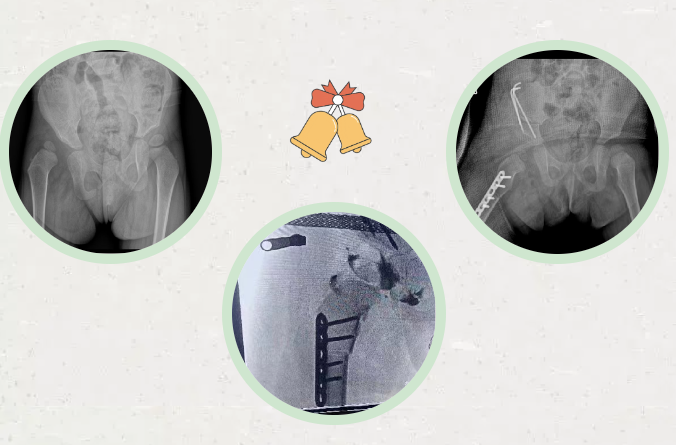

拍摄X光片后

王永堂告诉贝贝妈妈

贝贝存在发育性髋关节脱位

(DDH)

而且因为已经2岁

年龄大了

建议行

Salter骨盆截骨术

1月26日

由徐刚教授主刀

为贝贝完成

采取的是以前缘缺损为主的

髋关节发育不良的经典手术方案

术中切断部分内收肌

“T”形切开关节囊

复位脱位的髋关节

股骨近端去旋转短缩截骨

Salter骨盆截骨

术后进行髋关节人字石膏固定

手术非常成功